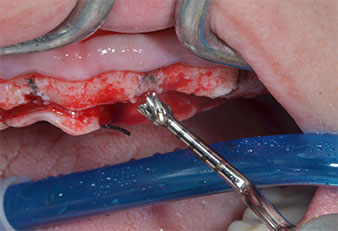

Пиезоелектрически инструмент с диамантено покритие с форма на пламък (Piezomed I1) e използван за маркиране на позициите на имплантите и за пилотна подготовка (Фиг. 3). Препарацията беше извършена с внимателни вертикални движения, с намалена мощност, пълна иригация и лек натиск (под 300 g) След това се приложи пилотен инструмент (Piezomed I2A/ I2P) за първоначално увеличение на диаметъра на имплантното ложе с 2 mm (Фиг. 4), последвано от 3 mm разширение (Фиг. 5)